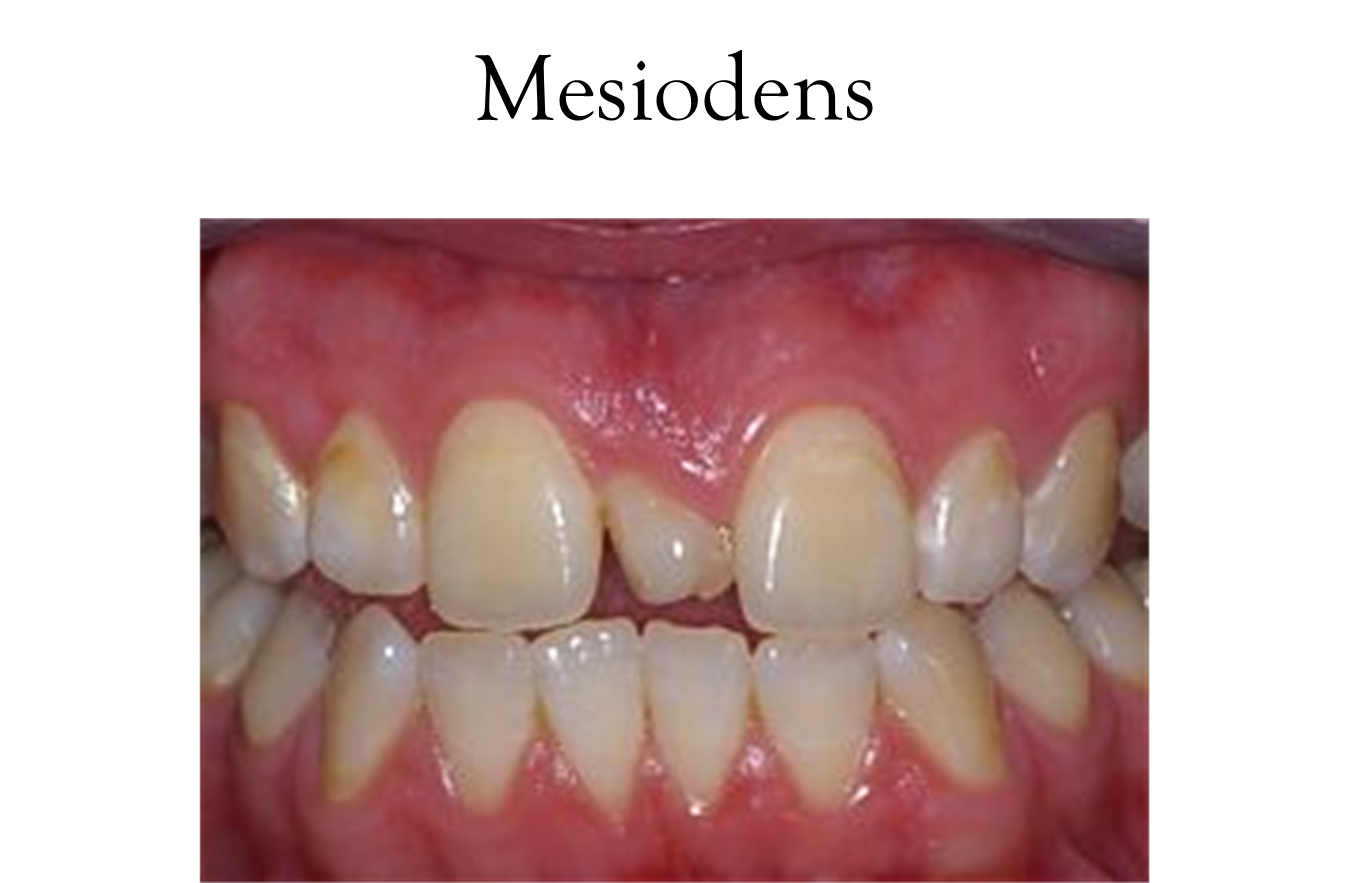

Referred to as extra teeth

More so with permanent than primary, more males than females.

Mesio= midline, Dens= tooth (i.e. central incisor)

Gardner’s Syndrome is another condition characterized by the occurrence of multiple, impacted supernumerary teeth

Also known as familial colorectal polyposis, an autosomal dominant form of polyposis

This disease is of interest to the dental profession because the presence of supernumerary teeth and multiple osteomas in the mandible and maxilla may lead to its diagnosis